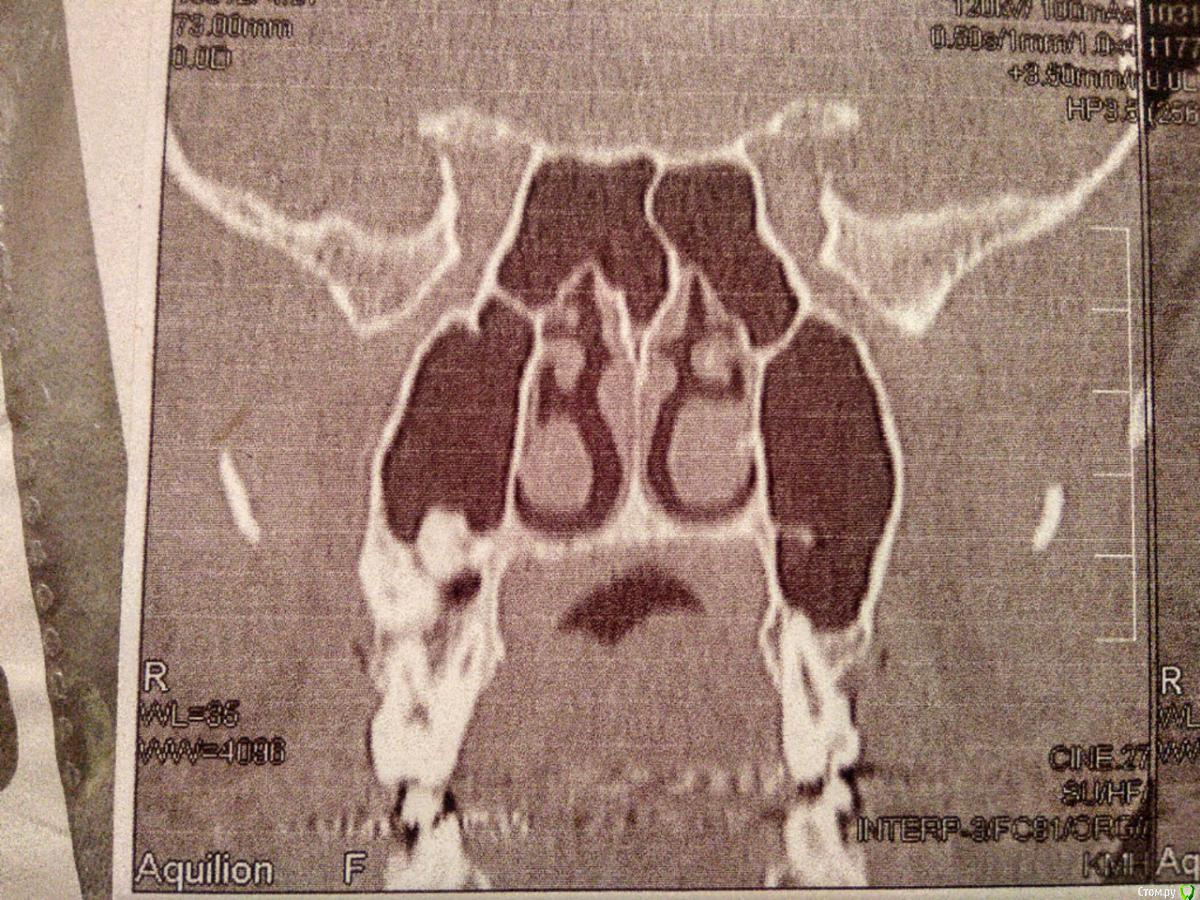

lader Опубликовано 29 декабря, 2019 Поделиться Опубликовано 29 декабря, 2019 (изменено) Месяц назад ставили пломбу на 7 левый сверху, сразу была дискомфортно, сейчас чувствую жжение в десне, есть температура 37.1 , частые потовыдиления. Был небольшой карман между десной и зубом врач его запломбировал. Зуб на фото видно немного пророс в гайморову пазуху, и на десне возле его есть затемнение. Что это может быть? Фото с кт гайморовых пазух Изменено 29 декабря, 2019 пользователем lader Ссылка на комментарий

lader Опубликовано 29 декабря, 2019 Автор Поделиться Опубликовано 29 декабря, 2019 (изменено) https://a.radikal.ru/a26/1912/2c/46bfc5db6f28x.jpg https://a.radikal.ru/a16/1912/a2/c056c9331357x.jpg На втором фото справа от зуба видно затемнение Изменено 29 декабря, 2019 пользователем lader Ссылка на комментарий